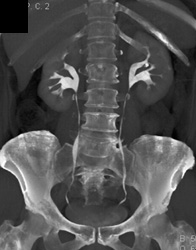

Diagnosis

Renal Calcification